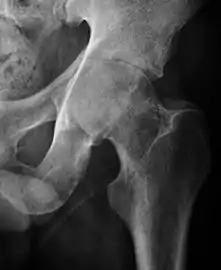

Projectional radiography ("X-ray") is currently useful not only in older people in whom osteoarthritis of the hip is suspected but also in younger people without osteoarthritis, who are being evaluated for femoroacetabular impingement (FAI) or hip dysplasia.[1]

Plain radiography allows us to categorize the hip as normal or dysplastic or with impingement signs (pincer, cam, or a combination of both). Besides these, pathologic processes like osteoarthritis, inflammatory diseases, infection, or tumors can also be identified (Figure 1).[1]

- Osteoarthritis

In adults, one of the main indications for radiographs is the detection of osteoarthritic changes (Figure 1(e)). Nevertheless, radiographs usually detect advanced osteoarthritis that can be graded according to the Tönnis classifications. The grading system ranges from 0 to 3, where 0 shows no sign of osteoarthritis. Intermediate grade 1 shows mild sclerosis of the head and acetabulum, slight joint space narrowing, and marginal osteophyte lipping. Grade 2 presents with small cysts in the femoral head or acetabulum, moderate joint space narrowing, and moderate loss of sphericity of the femoral head. Grade 3 is the severest form of osteoarthritis, which manifests as severe narrowing of the joint space, large subchondral cyst with productive bone changes that may lead to deformity of the bone components of the joint, while secondary osteoarthritis due to calcium pyrophosphate deposition can be diagnosed when calcification of hyaline cartilage and fibrocartilage is detected.[1]

There are other pathological conditions that can affect the hip joint and radiographs help to make the appropriate diagnosis. Acute bacterial septic arthritis can be diagnosed by radiographs when a fast regional osteoporosis and destructive monoarticular process develops (Figure 1(f)). In case of tuberculous or brucella arthritis it is manifested as a slow progressive process, and diagnosis may be delayed.[1]